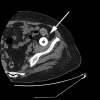

Dislocation of the trial femoral head is a rare and unpleasant event that can compromise the success of the total hip arthroplasty. A 62-year-old Caucasian woman with osteoarthritis was admitted to our Department and underwent an elective total hip arthroplasty. While performing the dislocation manoeuver the trial femoral head dissociated from the taper in the superior and anterior direction in the soft tissue and could not be retrieved immediately. The operation was then executed and finished in an ordinary manner. Three months after discharge from our department patient presented with the pain in the hip and groin and periprosthetic joint infection was diagnosed. The successful second operation for the retrieval of the dislocated trial femoral head was conducted through ilioinguinal approach. In this paper we reviewed the published literature and developed the algorithm for the decision-making while dealing with the dislocated and lost trial femoral head.